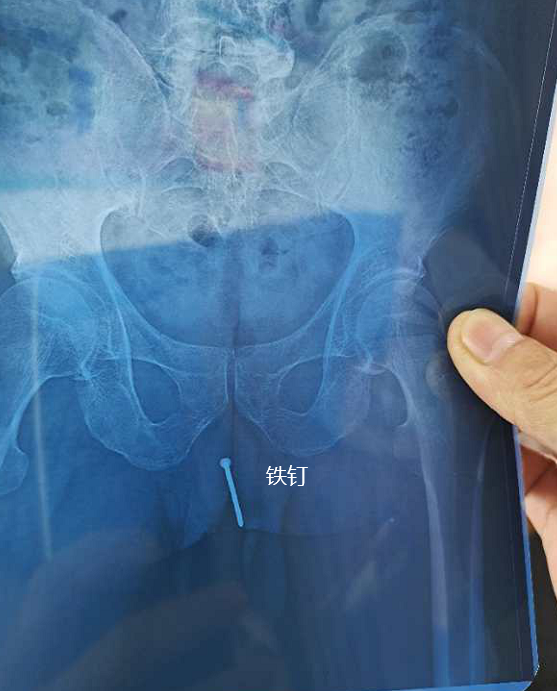

泸州合江男子竟将5厘米长生锈钉子塞进尿道

图片尺寸557x691